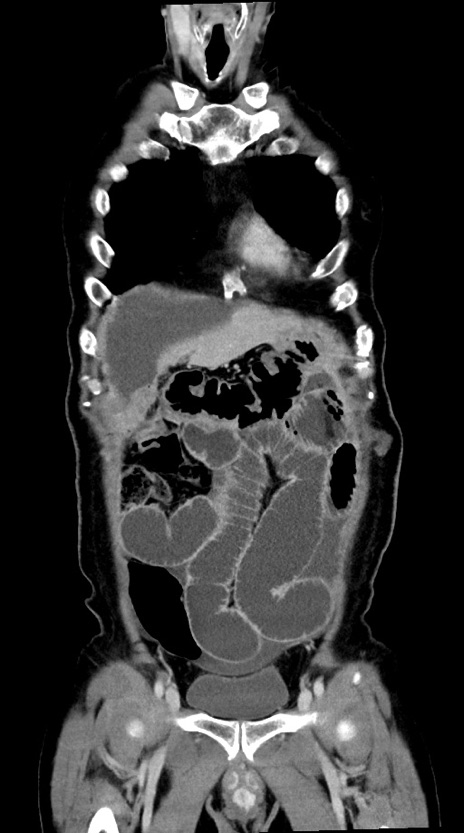

横断像

【症例】60歳代男性

【主訴】嘔吐

【現病歴】胃癌にて胃全摘後。食思不振が悪化し、夜中に嘔吐することがある。

【既往歴】胃癌、胃全摘、脾摘、胆摘後

【データ】WBC 5900、CRP 10.56